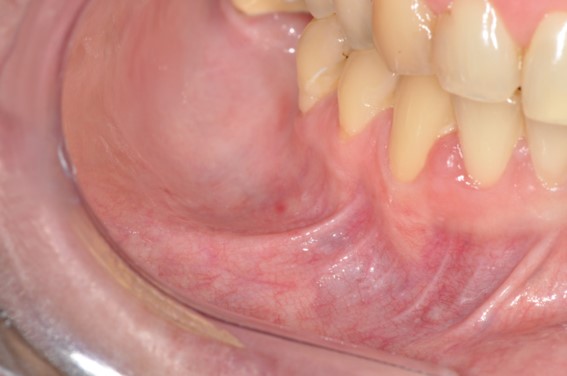

The patient was referred to the Oral Medicine Department, and the intraoral examination revealed a healthy oral mucosa, no recent tooth extraction, no trauma, and no oral surgery (Figure 1).

As a result of the patient’s complaint, we identified a small area adjacent to the region of the right mental nerve that was uncomfortable on palpation. No other changes were found by means of cone-beam computed tomography (Figure 2A) and clinical examination. Magnetic resonance features made possible to identify a change in the mandibular body extending to the entire right side (Figures 22C, 33B), coinciding with the clinical complaint, indicating a probable mandibular medullary invasion.